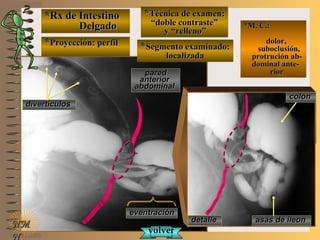

*Rx de Estómago*Rx de Estómago

**Proyección:Proyección:

**Técnica de examen:Técnica de examen:

A-A-

B-B-

C-C-